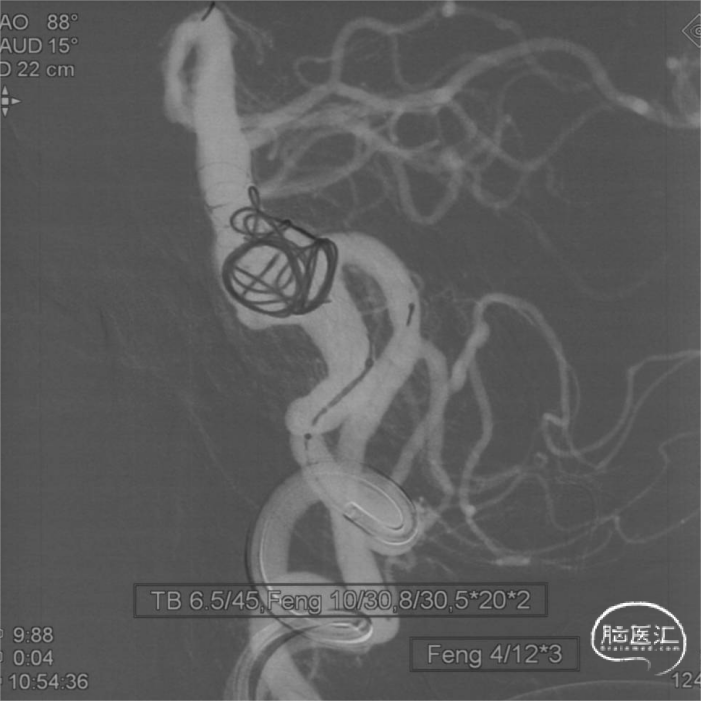

栓塞过程

微导管到位:

术后即刻

右侧椎动脉造影见血管重建满意;

术后右侧椎动脉正侧位造影:

左侧椎动脉正侧位造影:

模拟后建议使用支架型号:Tubridge 6.5mm/45m